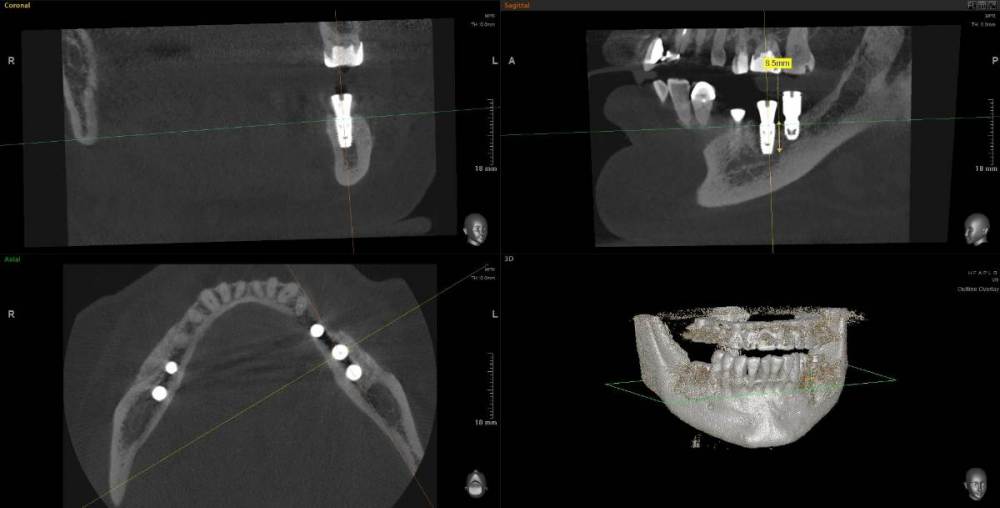

Kostoprav Опубликовано 11 мая, 2021 Поделиться Опубликовано 11 мая, 2021 (изменено) 70%ауто+30% ксено, мембрана цитофлекс, винты самосверлящие после пластики до установки имплантов прошло 8 мес. Изменено 11 мая, 2021 пользователем Kostoprav 3 6 Ссылка на комментарий

Карен Аванесов Опубликовано 12 мая, 2021 Поделиться Опубликовано 12 мая, 2021 20 часов назад, Kostoprav сказал: 70%ауто+30% ксено, мембрана цитофлекс, винты самосверлящие после пластики до установки имплантов прошло 8 мес. Замечательно! 1 Ссылка на комментарий